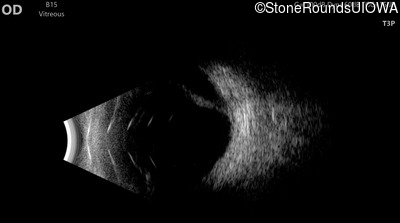

B-Scan Ultrasonography - Right - 20/600

Exemplar